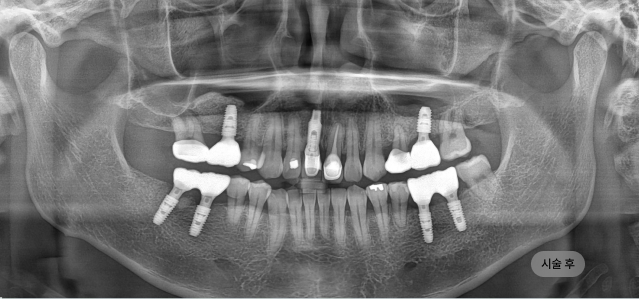

화면을 드래그하여 전/후를 비교해 보세요